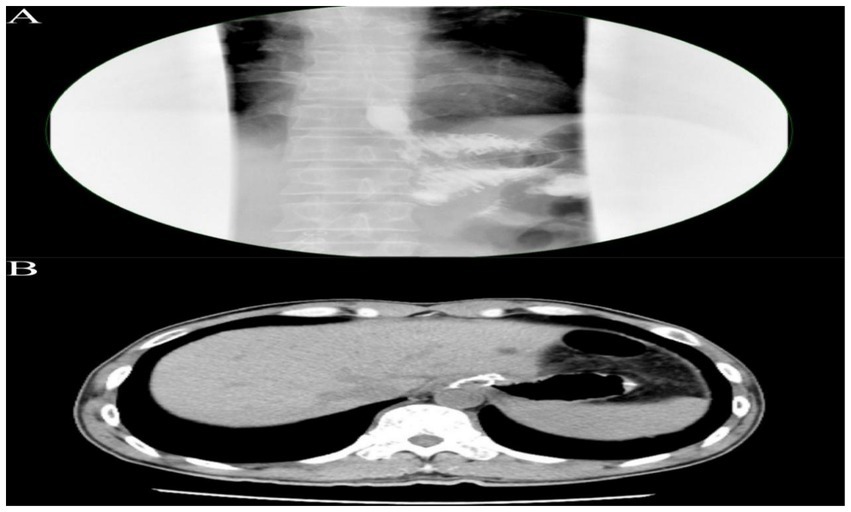

On postoperative day 3, the patient passed flatus and gradually resumed oral intake. Upper GI contrast on day 6 showed a patent anastomosis with smooth passage (Figure 4A). Sutures and the left upper abdominal drain were removed at 1 week. On day 12, abdominal CT confirmed anastomotic patency with no significant abnormalities (Figure 4B). The posterior esophagojejunostomy drain was removed, and the patient was discharged. Supportive care included albumin supplementation, nutritional support, regular dressing changes, and monitoring of liver and renal function. The patient recovered well, tolerated diet, albumin normalized, and no complications occurred. Pathology revealed marked mucosal fold hypertrophy, severe chronic active inflammation with erosion, congestion, edema, prominent foveolar hyperplasia with mucinous change, distortion, and dilation, foveolar extension to the muscularis mucosae, and reduced acid glands, consistent with Menetrier’s disease (Figure 3D). Immunohistochemistry: CEA (partial+), CK (broad-spectrum+), Ki67 (normal proliferative pattern), MUC-2(−), MUC-5 AC (foveolar+), MUC-6 (focal+), P53 (wild-type).

Figure 4. (A) Upper gastrointestinal contrast study demonstrating an esophagojejunostomy with an anastomotic diameter of approximately 0.6 cm. The contrast agent traverses slowly but smoothly, with no significant leakage observed around the anastomosis. (B) Abdominal CT scan reveals the esophagojejunostomy, showing a circumferential metallic density shadow, with the anastomosis appearing patent.